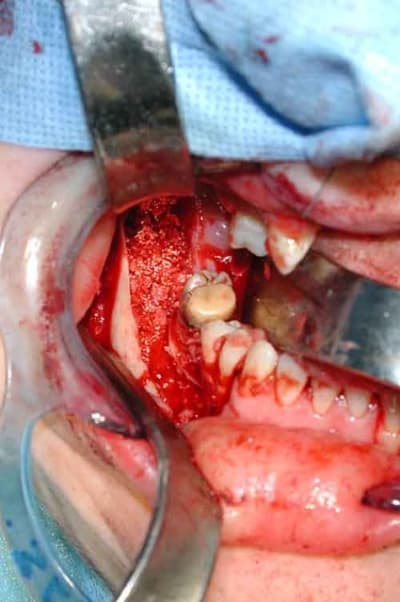

Bref, en ce qui concerne ce cas (assez récent), je vous livre le raisonnement qui a été le notre : probables kystes péricoronnaires sur les dents incluses (il n'y a pas de dents "surnuméraires"...). Décision d'abord chirurgical pour énucléation des 3 kystes (les ponctions ne "marchent" pas dans ces lésions) et examens anatomopathologiques extemporanés pour décider, en per-opératoire, de la conduite à tenir (photo 1).

Diagnotic extemporané : kératokystes (!). Les dents incluses se sont donc avérées être un piège diagnostic! Le traitement s'est de ce fait contenté d'un curetage appuyé des paroies osseuses, conservation des 2 nerfs dentaires et, en raison de la taille des kystes mandibulaires et du risque de fracture post-opératoire, nous avons y avons associé une greffe (hydroxyapatite + os autologue (crête illiaque) + PRP) au niveau mandibulaire uniquement (photos 2 et 3)et blocage intremaxillaire pendant 15 jours.

Les suites ont été simples, la reminéralisation des kystes est actuellement en cours (photo 4) et la sensibilité des V3 est normale.